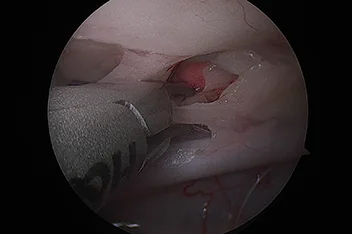

관절경

개,고양이 들은 다양한 관절질환이 존재하고, 복합적으로 존재하는 경우도 빈번합니다.

정확한 진단이 나지 않은 뒤 수술을 하게되면 증상개선이 더디거나 개선이 안될 수 있어, 정확한 진단이 필요합니다.

관절의 경우 X-ray 촬영등으로 진단의 한계가 명확하며, 상위 검사인 CT, MRI 촬영으로도 진단의 한계가 있습니다.

이때 관절경은 내부 구조물들을 직접 시각화 하여 보다 정확한 관절의 상태를 확인하고 진단할 수 있으며, 진단과 치료를 동시에 진행하는 경우도 있습니다. 대표적으로 십자인대단열(CCLR), 골연골염(OCD), 자뼈꿈치돌치유합부전(UAP), 내측관상돌기질환(MCD) 등에 활용될 수있습니다.

관절경 팔꿈치관절(Elbow) 확인

관절경 무릎관절(Stifle) 확인 (반월판 및 십자인대)

* 리본동물의료센터 케이스 사진으로 무단 복제 및 도용을 금지합니다.